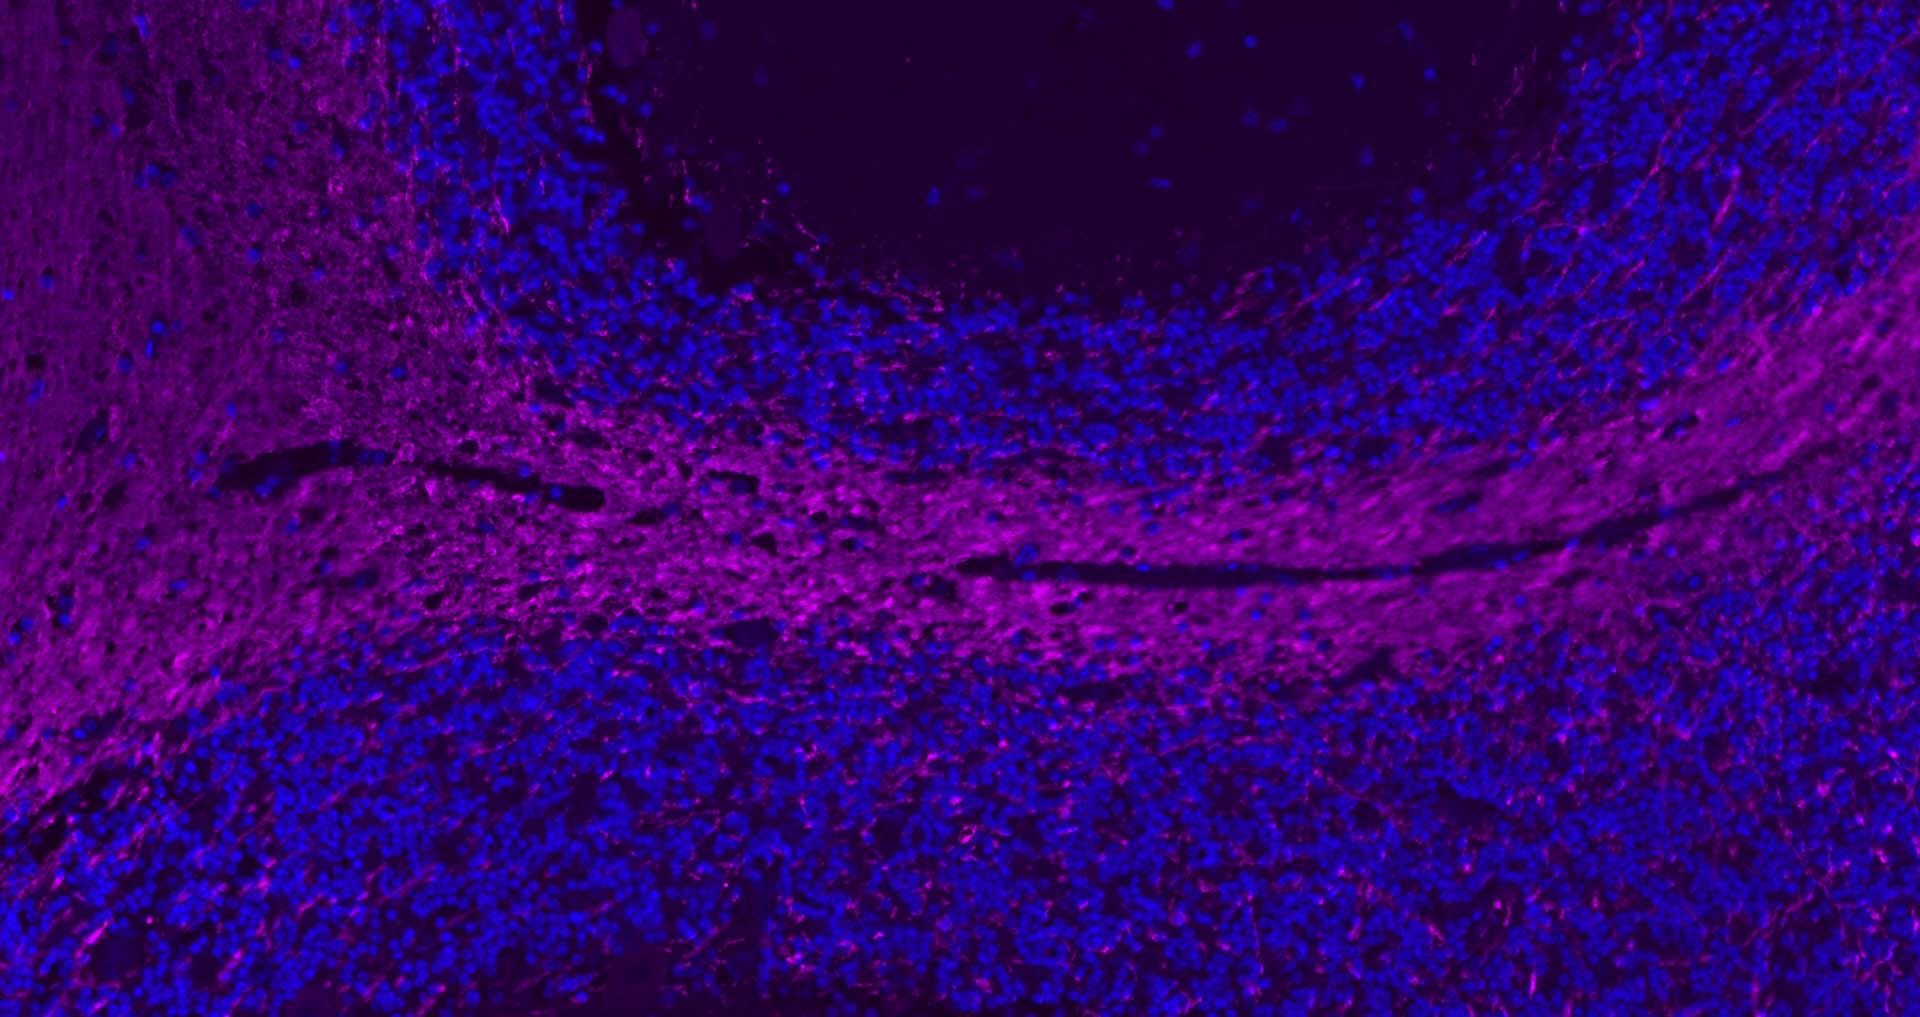

Paraformaldehyde-fixed, paraffin embedded Mouse Small Intestine; Antigen retrieval by boiling in sodium citrate buffer (pH6.0) for 15 min; Antibody incubation with CHGA Polyclonal Antibody, Unconjugated (bs-43559R) at 1:200 overnight at 4°C. Followed by conjugated Goat Anti-Rabbit IgG antibody (Purple, bs-0295D-Cy5), DAPI (blue, C02-04002) was used to stain the cell nuclei.